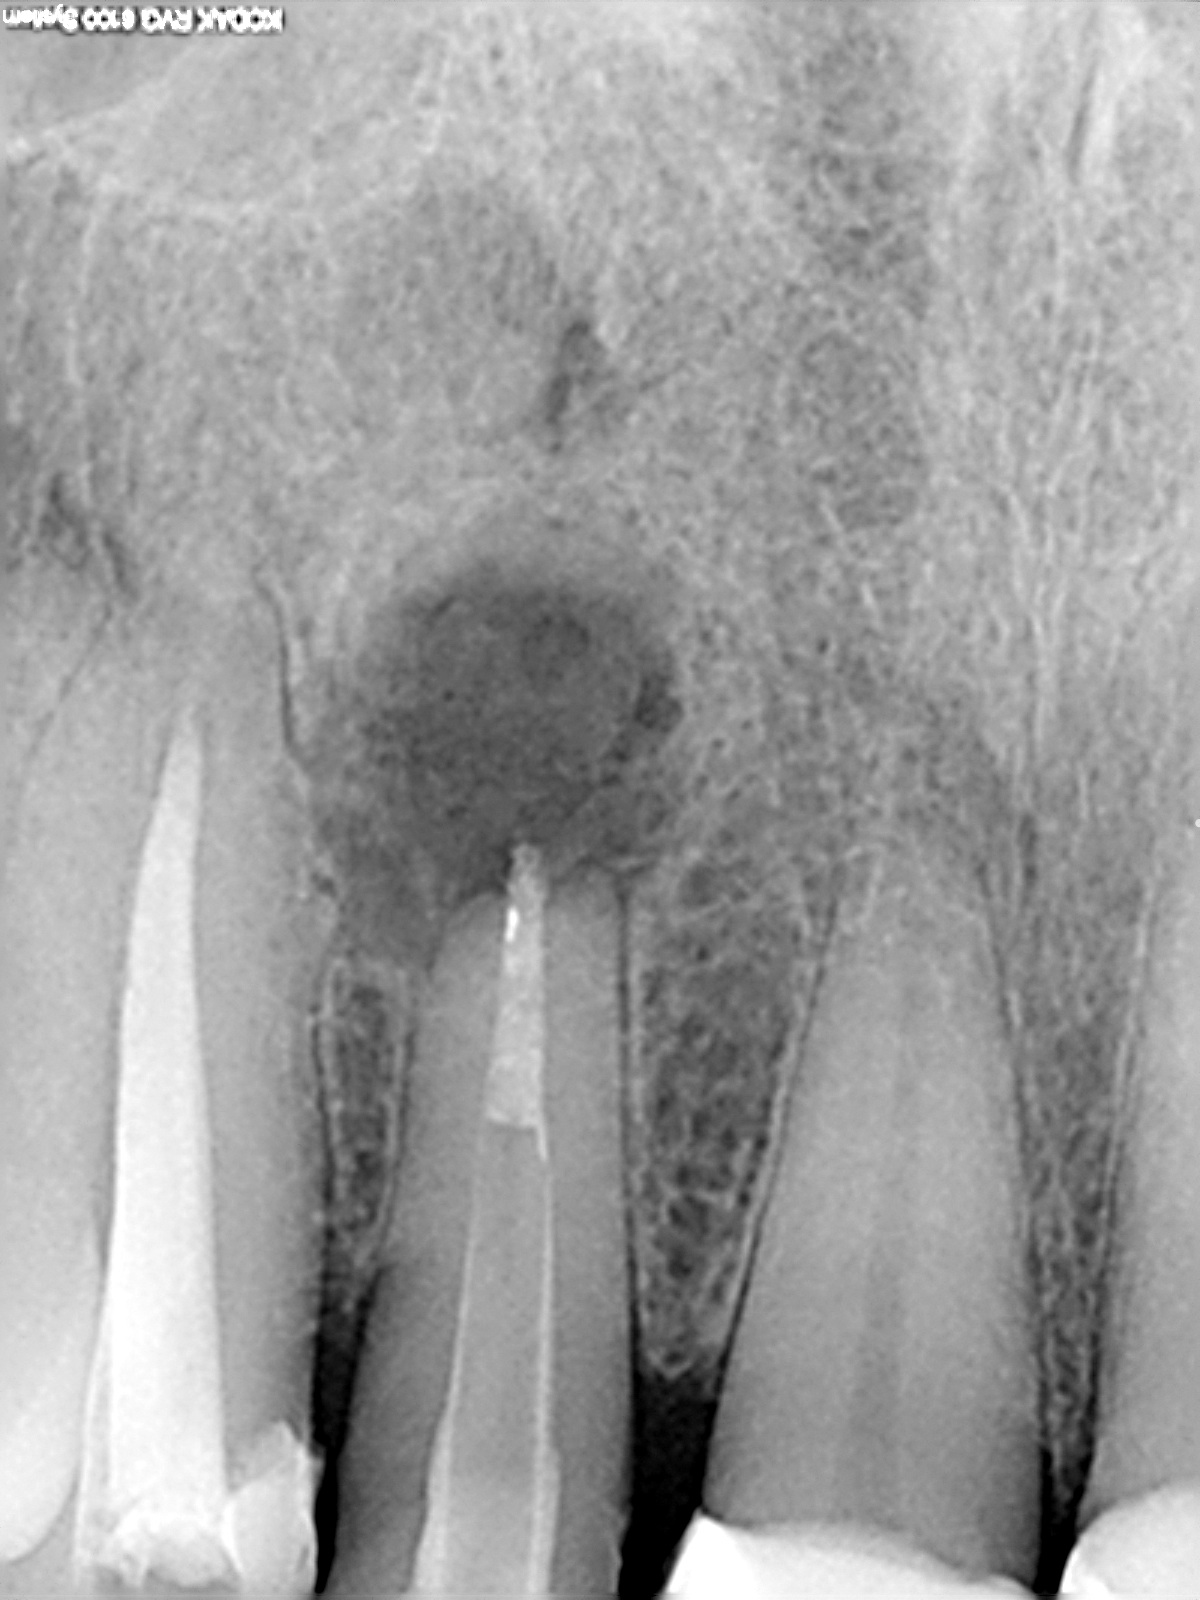

2 Jahresrecall

1200 × 1600

WSR